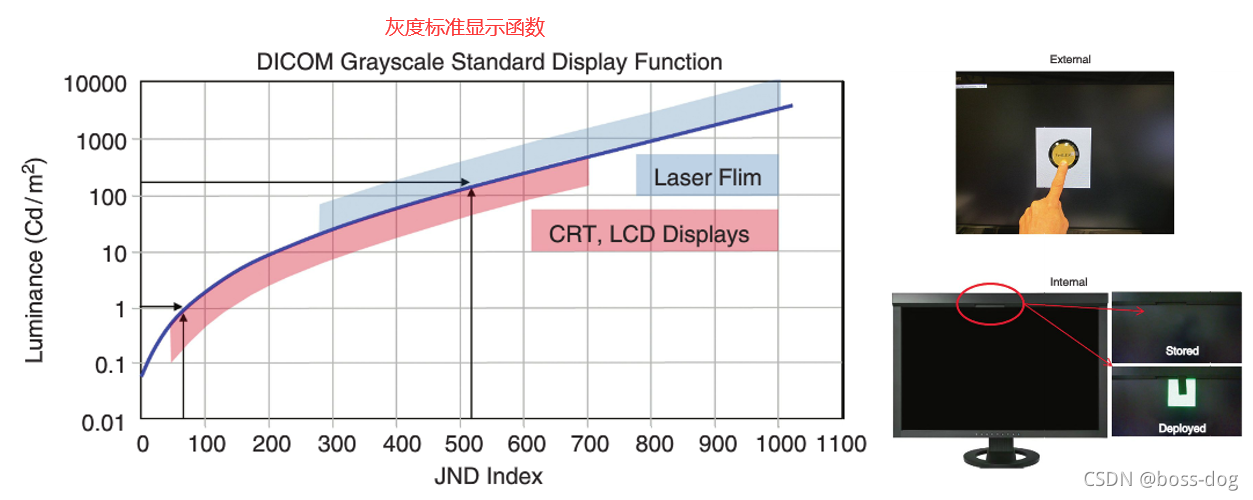

DICOM GSDF

显示器需要调,我们的显示器用的时间长了以后,它的颜色显示可能就会出现一个弱化,那么需要进行调节,将原始的图用黑白色在屏幕上面的亮暗进行最优的显示。

DICOM(医学数字影像和通讯)有个标准叫GSDF,用来把屏幕的显示进行优化校准,目前的显示器都有一键校准的功能。

- PS 3.14: Grayscale Standard Display Function(灰度标准显示功能)